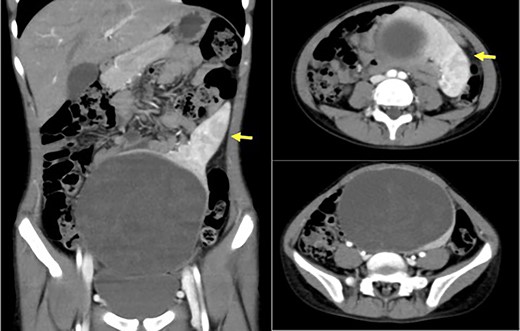

The patient was a 10-year-old girl. She visited our hospital after her grandmother noticed a mass in her lower abdomen that she had been aware of for 6 months. Abdominal ultrasonography revealed that she had a large mass centered in her lower abdomen. The tumor border was clear, the internal structure was heterogeneous and the blood flow was poor (Fig. 1). We suspected an ovarian tumor, but blood tests showed no elevated tumor markers such as AFP and CA19–9. Abdominal magnetic resonance imaging revealed a cystic mass 10 cm in diameter with high intensity on T1-weighted images and high intensity on T2-weighted images (Fig. 2). Abdominal computed tomography revealed a spleen near the navel and a cystic lesion with poor contrast that continued from the lower pole of the spleen (Fig. 3).

Abdominal computed tomography revealed a spleen (arrows) near the navel and a cystic lesion with poor contrast that continued from the lower pole of the spleen.